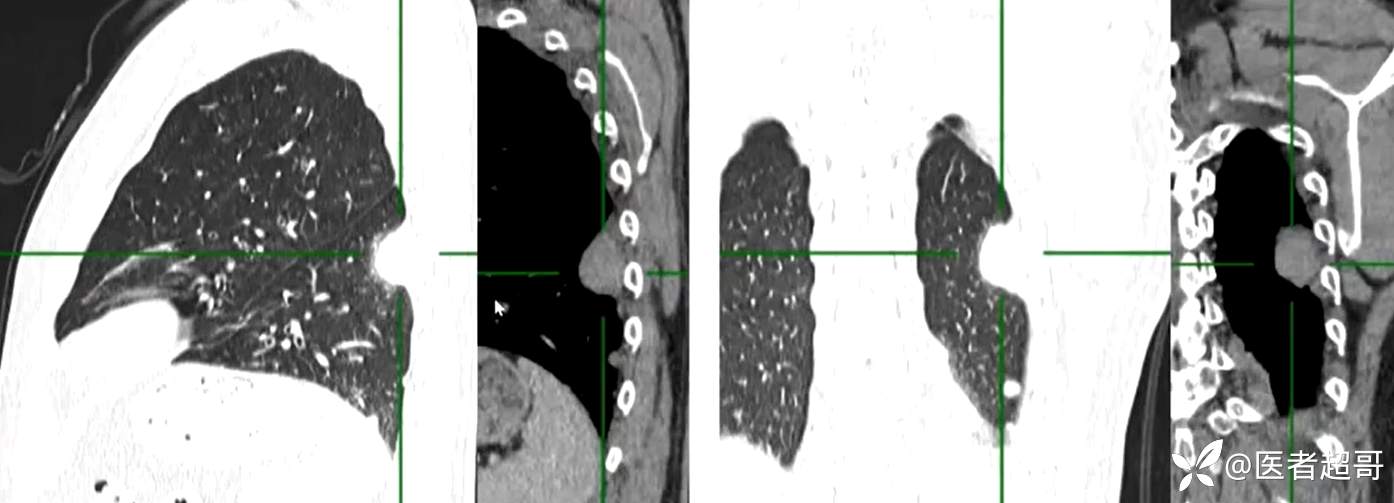

现病史:患者5月前因咳嗽、咳痰于当地医院就诊,完善胸部CT提示:胸膜多发占位,期间患者无胸闷、气紧、咳嗽、咳痰、心慌等不适,患者于我院门诊行胸部CT提示:左下胸膜增厚并见多个软组织密度结节影局限性凸起,较大者大小约3.5x2.2cm,增强扫描呈持续性轻度强化,考虑肿瘤性病变可能性大;门诊遂以:胸膜肿瘤收入我科。